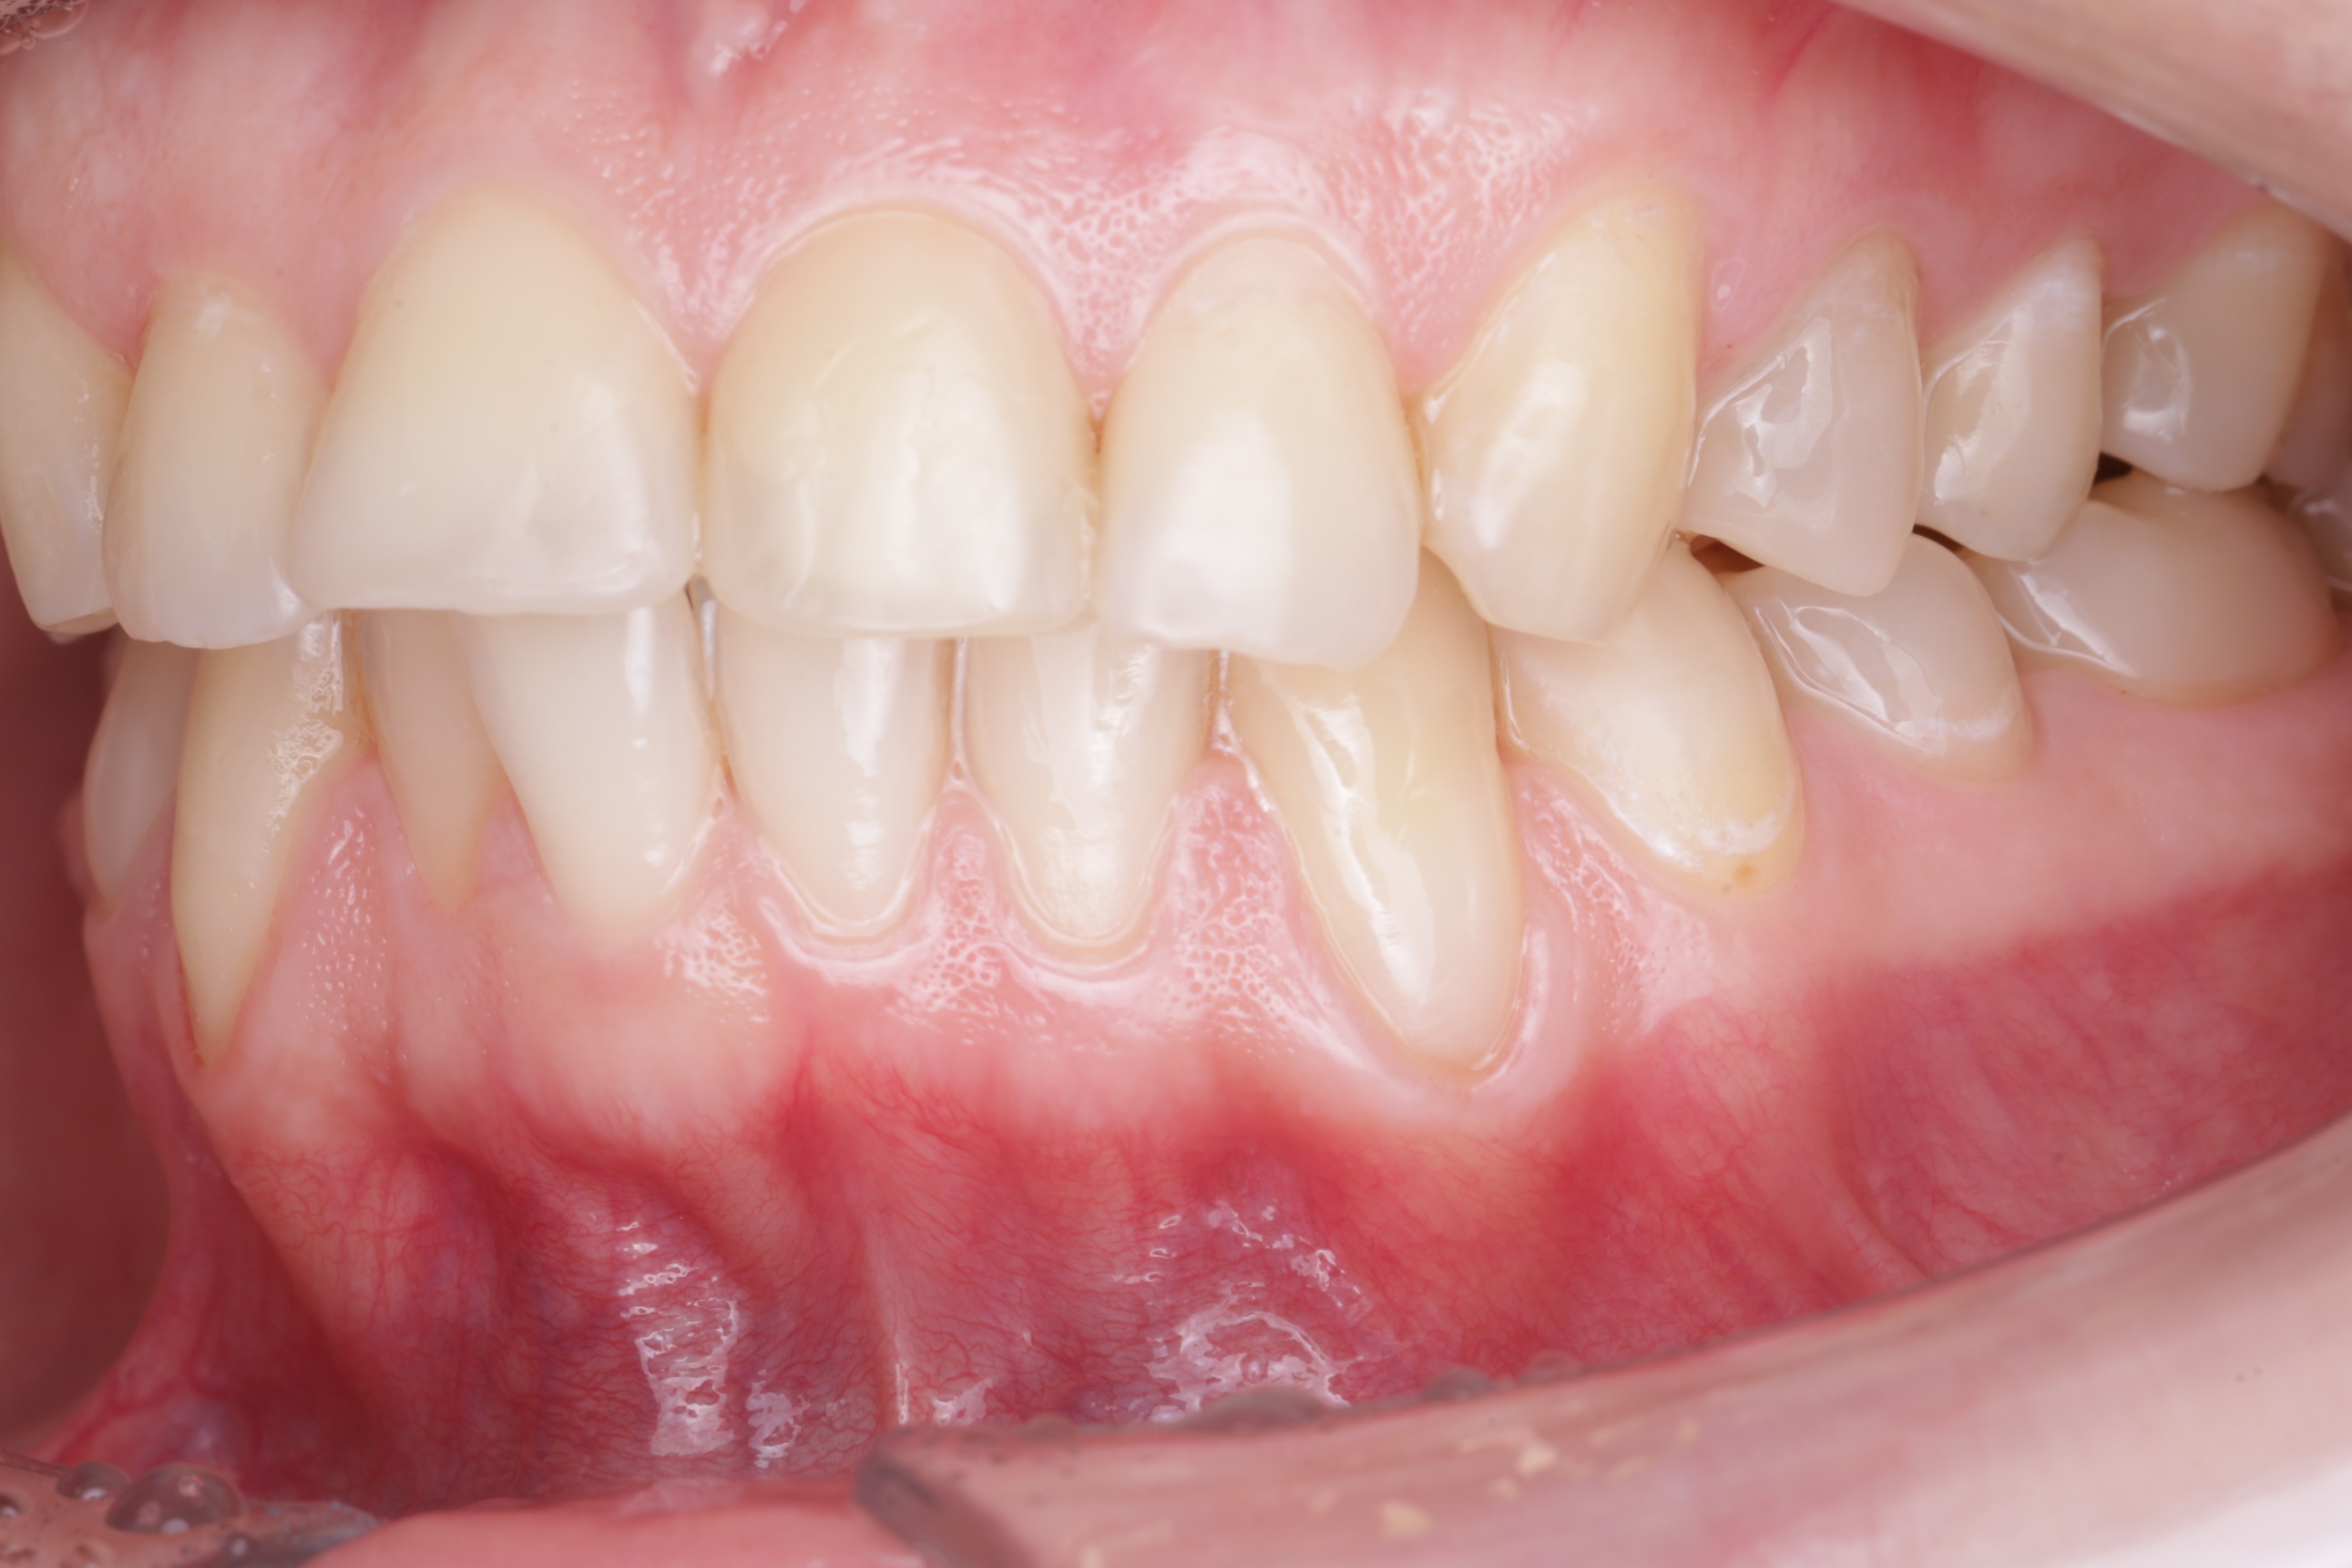

К нам обратилась пациентка 27 лет с желанием сделать красивую улыбку с ровными и красивыми зубами. На фотографии мы видим выраженные рецессии десны на нижних клыках, несостоятельные пломбы, скученность и стираемость.

В данной клинической ситуации было принято решение провести санацию полости рта, затем закрыть рецессии в области нижних клыков и только потом приступить к ортодонтии.